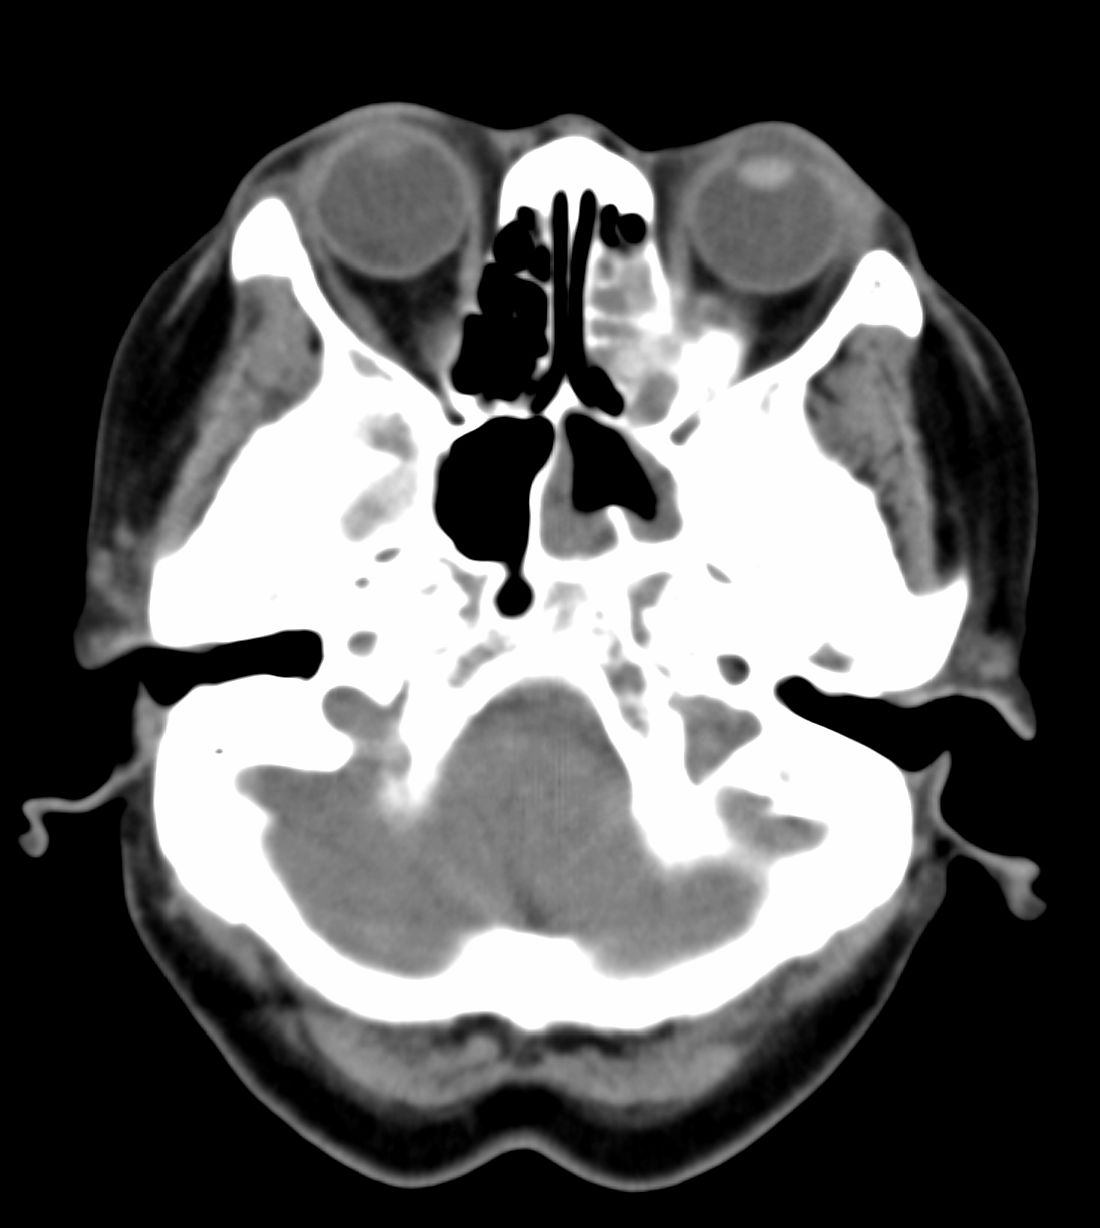

女,69岁。鼻出血2月多。(会诊病史就这样简单)鼻副窦ct检查如下:

左侧鼻腔及上颌窦见软组织块影,左侧上颌窦腔扩大,骨质吸收,右侧上颌窦见半圆形软组织密度影,鼻中隔向右侧弯曲,左侧鼻和鼻窦内翻型乳头状瘤可能性大,建议增强。

左侧上颌窦及鼻腔内见软组织密度影,其内密度不均匀,见斑片状高密度影,右侧上颌窦腔明显扩大,窦壁吸收变薄,鼻中隔右偏,右侧上颌窦见一半圆形软组织密度影,边界清楚,其内密度均匀。诊断,1、左侧鼻腔及上颌窦内翻乳头状瘤可能性大,上颌窦癌,息肉及霉菌性上颌窦炎待除外。2、右侧上颌窦粘膜下囊肿。

1)考虑左侧上颌窦内翻乳突状瘤突入左侧鼻腔。2)副鼻窦炎,右侧上颌窦黏膜下囊肿。

病理:霉菌性左侧上颌窦炎伴左侧上颌窦纤维组织增生。

窦腔密度不均匀增高,无明显钙化征象,后外侧及内侧窦壁膨胀明显,局部破坏消失,筛窦受累及,但双侧对比发现左侧窦壁骨质有硬化增白现象,这可能是支持左侧霉菌性上颌窦炎的主要依据点。